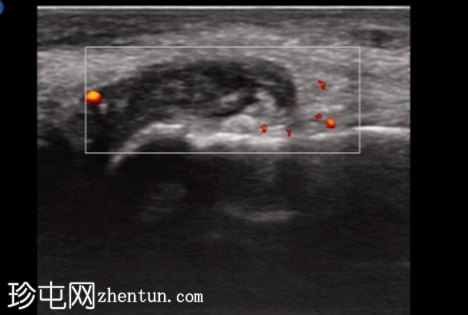

3.png

纵轴切面

第一跖趾关节纵轴切面

治疗后2周

关节积液伴轻度滑膜增生。高回声不规则沉积物,符合尿酸钠晶体沉积的典型表现。彩色多普勒成像显示滑膜充血活跃,符合急性炎症活动。